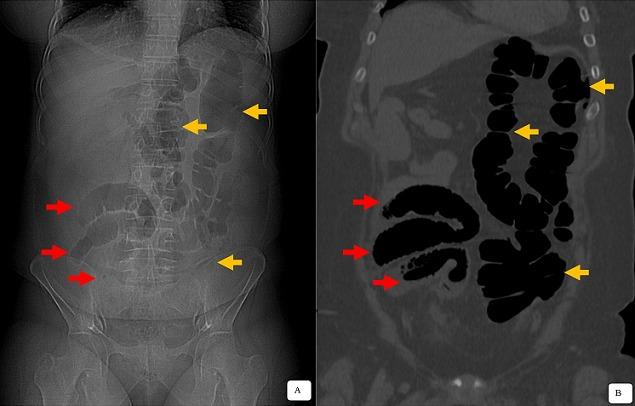

Complete common mesentery is a rare abnormality in midgut rotation. Its detection is exceptional during adulthood because, during this period, is very often asymptomatic and therefore not diagnosed. Complete common mesentery may be discovered incidentally in patients with ectopic appendicular syndrome, as in our case study. We here report the case of a 42-year old patient presenting with acute clinico-biological pelvic inflammatory disorder. CT scan allowed the diagnosis of complete common mesentery associated with acute appendicitis. Laparotomy confirmed the diagnosis of perforated acute appendicitis associated with intestinal malrotation. Appendectomy outcomes were favorable.

完整的共同肠系膜是中肠旋转罕见的异常情况。在成年期其检出极为罕见,因为在此期间它常常没有症状,因此未被诊断出来。完整的共同肠系膜可能在异位阑尾综合征患者中偶然发现,就像我们的病例研究那样。我们在此报告一例42岁患者,其表现为急性临床生物学盆腔炎症性疾病。CT扫描诊断为完整的共同肠系膜合并急性阑尾炎。剖腹手术证实诊断为穿孔性急性阑尾炎合并肠旋转不良。阑尾切除术后结果良好。